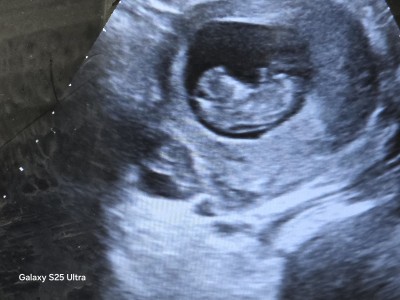

Kizlar tahmin edelim

Gebelik haftası 11+1

Erkeğe benzettım hayırlısı olsun

Kesenin cinsiyetle alakası yok benimde kesem yuvarlaktı  bebeğim erkek yani içimden geceni söyliyim erkeğe benziyor rabim gönlüne göre versin